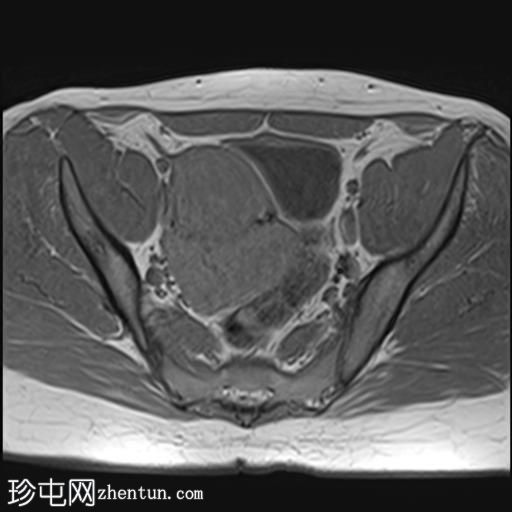

轴位

T2加权像

2.jpg

盆腔内可见多个边界清晰的肿块:

其中一个位于子宫上方,T2加权像呈中等信号,中心区域呈高信号,增强T1脂肪抑制像未见强化。右侧卵巢增大,增厚的血管蒂扭曲,未见强化,轴位和矢状位T2加权像均显示清晰。

另一个位于子宫后窝,T2加权像呈中等信号,增强扫描显示明显强化。

轻度腹腔积液